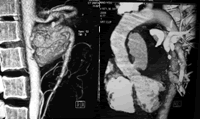

入院后初步检查发现,WBC及Neut比例正常偏高,炎症指标ESR和CRP明显增高。考虑:(1)感染性疾病 无明确感染灶,抗生素治疗无效,常见的病毒血清学均阴性,目前感染无证据。(2)肿瘤 无浅表淋巴结和肝脾肿大,肿瘤标志物正常,常见可引起发热的实体肿瘤如淋巴瘤、肝癌、肾癌、胃肠道肿瘤等均无证据。 UCG提示主动脉后壁及左房旁占位,需要进一步明确性质。(3)结缔组织疾病 青年男性,无其他系统性结缔组织疾病的特征性症状,且ANA、抗 ds-DNA、ANCA、肌酶谱均正常,临床不支持系统性红斑狼疮,多发性肌炎或皮肌炎、ANCA相关血管炎等常引起发热的结缔组织疾病。患者有腰痛,但与活动无关,无其他关节症状,血HLA-B27 阴性,腰椎MRI未见椎间盘和椎骨边缘的增生或纤维化,不支持血清阴性脊柱关节病如强直性脊柱炎。 入院后患者仍低热、腰腹痛性质同前,入院第6日出现剑下剧痛,不放射,持续不缓解。查体:剑突下偏左可触及搏动性包块,听诊血管杂音响亮,左侧肾动脉可闻及血管杂音,余同入院查体。临床上高度怀疑主动脉夹层或动脉瘤破裂,遂急查血管超声,提示肠系膜上动脉(SMA)起始段动脉瘤5 cm×6 cm。近期UCG发现的胸腔内病变是否也为血管病变?急查经食道超声心动图,提示升主动脉瘤6.9 cm×6.1 cm。增强CT+血管成像(CTA)进一步明确了上述诊断〔图1,图2〕:升主动脉根部及SMA根部动脉瘤形成,主肺动脉可疑偏心血栓形成,左肾动脉受压移位。诊断:多发大动脉动脉瘤,系统性血管炎。

图1 腹部增强CT血管重建:肠系膜上动脉动脉瘤

图2 胸部增强CT血管重建:升主动脉动脉瘤, http://www.100md.com